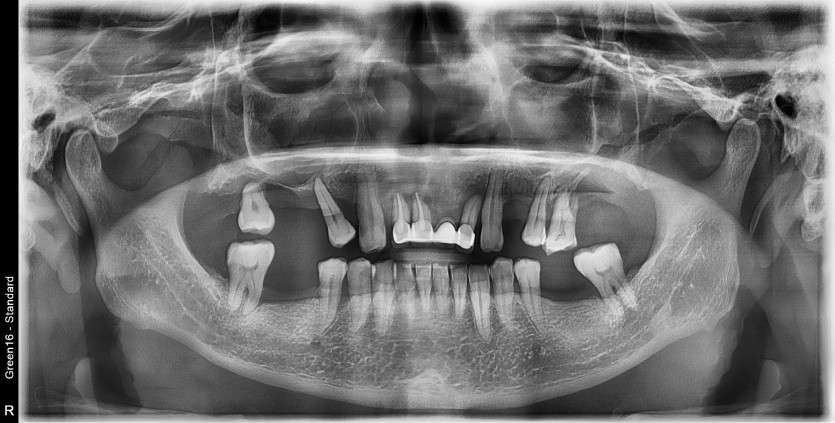

상악 풀아치 임플란트 증례입니다.

6개의 임플란트로 완성하였습니다.